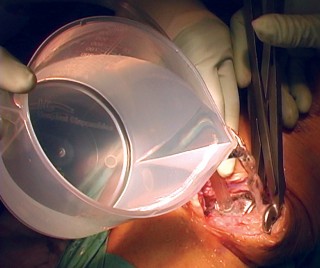

Cementing Technique and Implant Implantation

The hallmark of a cemented TKA is the creation of a durable, interlocking micro-mechanical bond between the host trabecular bone and the polymethylmethacrylate (PMMA) bone cement. PMMA is not an adhesive; it functions as a grout. Therefore, meticulous bone bed preparation is the single most critical factor in preventing aseptic loosening. The resected bony surfaces must be aggressively cleansed using pulsatile lavage to remove marrow, fat, and debris, exposing the porous cancellous bone. Sclerotic areas should be perforated with a small drill bit to enhance cement interdigitation.

The bone must be thoroughly dried immediately prior to cement application. High-viscosity cement is typically mixed under a vacuum to reduce porosity and increase fatigue strength. The cement is applied during its "doughy" phase to both the implant surfaces and the prepared bone. The components are then impacted into place.

Crucially, the cement must be pressurized into the cancellous bone to achieve a penetration depth of 3 to 4 mm. Once the components are seated, all extruded peripheral cement must be meticulously removed with a curette, particularly from the posterior aspect of the condyles and the posterolateral corner, where retained cement fragments can cause severe postoperative pain, third-body wear, or impingement. The knee is then held in full extension with axial compression applied until the exothermic polymerization process is complete and the cement is fully cured.